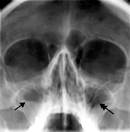

1 2 3

Рис.1. Рентгенограммы: 1 – гайморовые пазухи (норма); 2 – гайморит; 3 – постороннее тело в головном мозге – пуля|шар|.